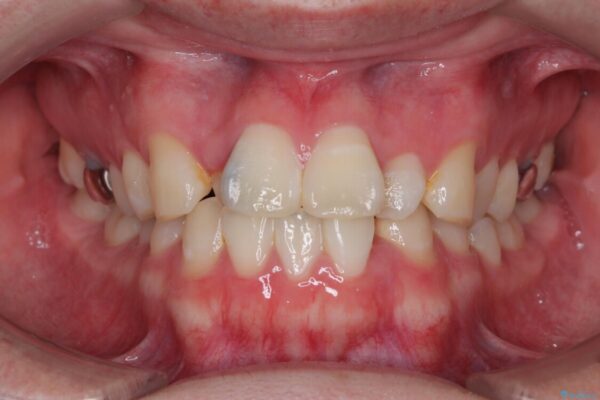

「歯並びがデコボコしていて、上下の中心がズレているのが気になる…」という悩みで来院された患者さまの症例をご紹介します。

・上下ともに歯がきれいに並びきらず、がたつきが見られました。

・上下の前歯の中心(正中)がずれています。

治療前

• 1年でここまで変わる!歯列のがたつきと正中のズレを改善した矯正治療(メタルブラケット×MARPE) 治療前画像